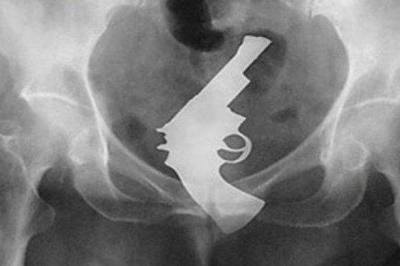

Women Attempts To Hide Loaded Handgun From Police In Her Vagina

27-year-old Anika Witt was recently arrested along with fellow passenger Clinton McDonald, 29, after being caught speeding in Bloomington Missouri. When officers searched the woman and the car, they found heroin concealed in her bra, along with ecstasy being found inside the vehicle.

The biggest surprise to the officers, however, is when she was transported to McLean County jail, where new arrivals are required to do a strip search. It was during this search that a female officer discovered a loaded .380 caliber handgun in Witt’s vagina, with police saying it had a bullet in the chamber.

Witt has since pleaded guilty to possession of a weapon by a felon, and the unlawful possession of a controlled substance. These charges mean that she could be facing up to 25 years in jail; 10 for the weapon charge and 15 for the drug charges. Witt made a plea agreement, with the state dismissing four felony counts which include armed violence - which carries a mandatory prison sentence of 6 to 30 years.

A sentencing date has been set for June 27th, and Witt has agreed to testify in court against McDonald, who is being charged with the unlawful possession of heroin with the intent to deliver the drug, and unlawful possession of ecstasy.